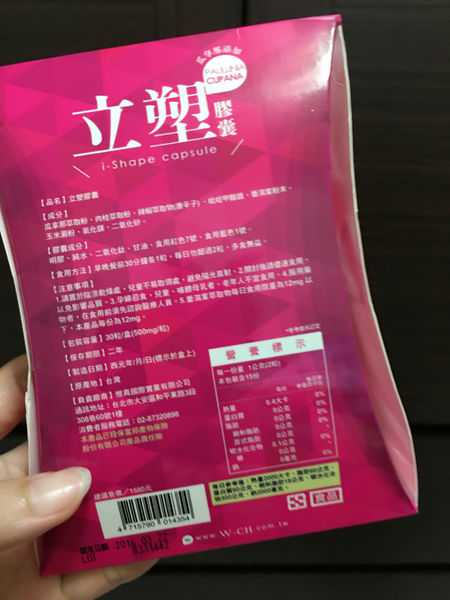

每一盒Supercut塑魔纖立塑膠囊都有三小包,每一小包有10顆膠囊

Supercut塑魔纖立塑膠囊的成分有:瓜拿那萃取粉、肉桂萃取粉、辣椒萃取物(唐辛子)、吡啶甲酸鉻、番瀉葉粉末、玉米澱粉、氧化鎂、二氧化矽。

食用方式:早晚餐前30分鐘各1粒,每日不超過2粒。(多食無益)

包裝是桃紅色的

番瀉葉萃取物每日食用限量為12mg以下,